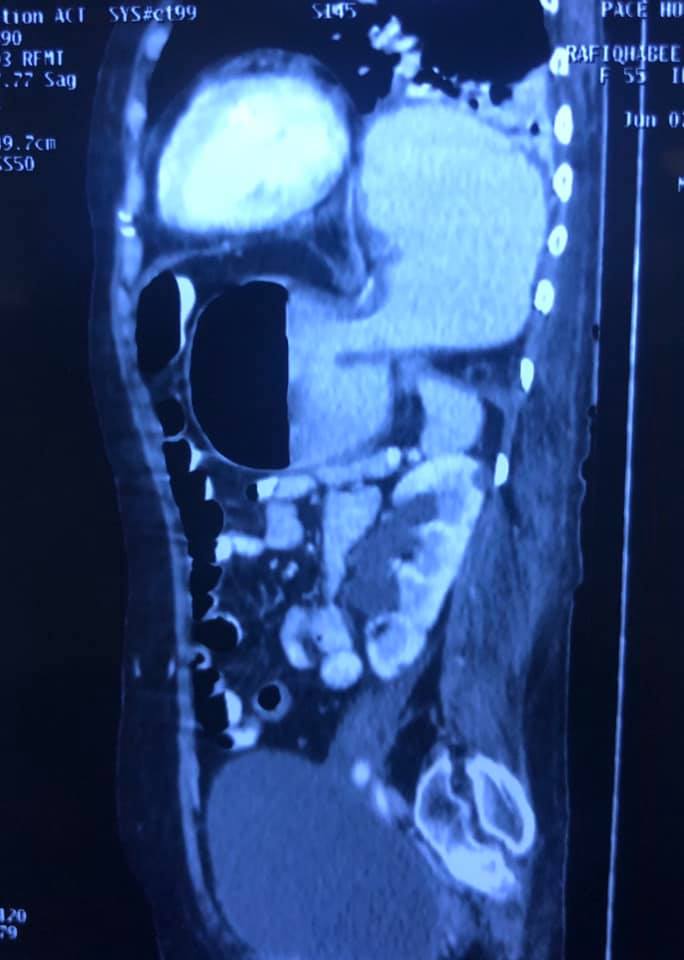

Challenging emergency during the COVID: Child’s A CLD with HUGE gastric varices uncontrolled

Child’s A CLD with HUGE gastric varices uncontrolled by Endoscopic glue and attempted EUS coiling. One salvage option would be TIPSS with balloon vascular occlusion but due to logistics we went for modified sugiura procedure. Splenectomy + Gastro esophageal devascularisation with anterior Gastrotomy and overseeing of gastric varices with pyloroplasty. Images show 1 CECT showing large gastric fundal varices. 2,3,4 Gastro Esophageal devasc 5, 6 Large fundal varices before and after oversewing. 7. Anterior gastrotomy 8. Pyloroplasty. Postoperative recovery was uneventful.